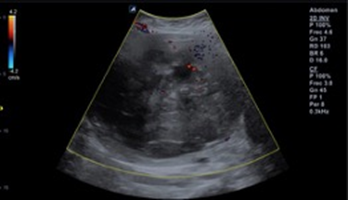

Admission laboratories highlight the blood count with leukocytes: 8000, hemoglobin 8g/l, hematocrit: 24%, platelets 250,000,000, rest of laboratories without alterations, ultrasonography 11.28.2021 tumor in pelvic cavity dependent on uterine body of 14 is reported cm, heterogeneous, with fine echoes inside, without data of vascular alterations, endometrium not visible, ovaries not visible (Image 1).

Image 1 Pelvic ultrasound. The anatomical topography of the uterus shows the presence of an oval image with lobulated edges and heterogeneous echogenicity due to solid areas with a cystic appearance (white arrow), which shows partial flow saturation after applying the color Doppler modality.